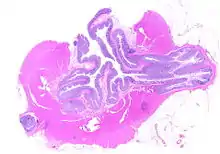

Diverticulosis is the condition of having multiple pouches (diverticula) in the colon that are not inflamed. These are outpockets of the colonic mucosa and submucosa through weaknesses of muscle layers in the colon wall.[1] Diverticula do not cause symptoms in most people.[2] Diverticular disease occurs when diverticula become clinically inflamed, a condition known as diverticulitis.[3]

The precise mechanisms by which diverticula are formed are unknown.[1] Multiple theories have been proposed including genetic susceptibility, diet, intestinal motility, changes in the microbiome, and inflammation. One leading theory suggests that diverticula form in weakened areas of the colon wall that are subjected to increased pressure.[1] The strength of the colon wall is known to decrease with age.[1] Previous theories proposed that impacted fecal matter and certain foods would get stuck in diverticula (thereby causing trauma), which caused poor blood flow, death of the affected intestinal wall cells, and intestinal perforation.[1] Newer theories have called this paradigm into question.[1]